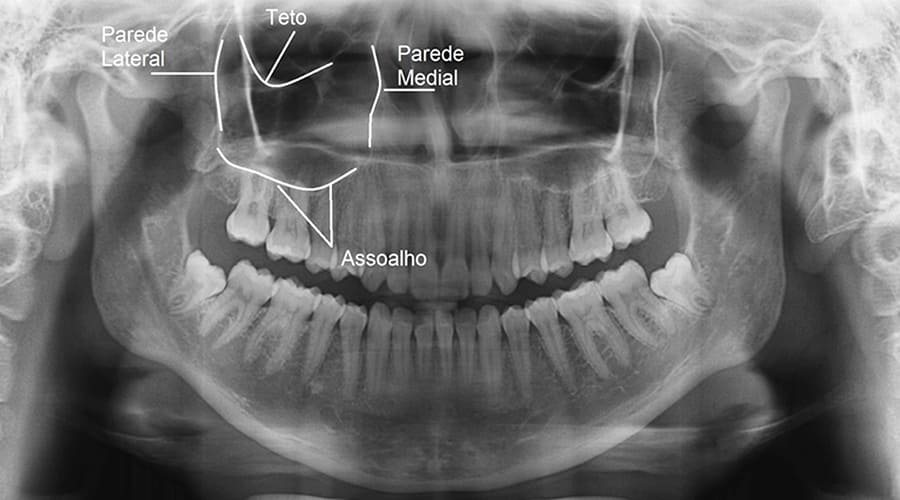

O seio maxilar é uma cavidade cheia de ar próximo ao nariz. Ele ajuda a aquecer e umidificar o ar respirado, e participa da ressonância da voz. Localizado no osso da maxila, logo acima das raízes dos dentes superiores posteriores, influencia diretamente a quantidade de osso disponível nesta região para a realização de procedimentos.

É nesse momento que o levantamento de seio maxilar (também chamado de cirurgia de seio maxilar) deve ser realizado. O procedimento reposiciona delicadamente a membrana do seio e cria espaço para o enxerto ósseo. O objetivo é formar uma base mais espessa e resistente, capaz de receber o implante com segurança.